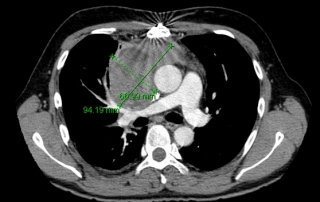

Scanner thorax abdomen pelvien : masse médiastinale antérieure et supérieure, absence d’atteinte du pédicule vasculaire, absence de nodule pulmonaire, scanner sous-diaphragmatique normal. Cible médiastinale taille 94 x 67 mm

TEP-FDG masse médiastinale hypermétabolique isolée